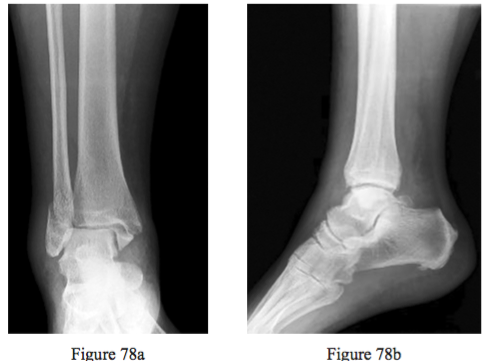

Question 78

Figures 78a and 78b are the radiographs of a 62-year-old woman with long-standing type 1 diabetes mellitus who fell and injured her right ankle. Her HbA1c level is 8%, or 64 mmol/mol. She has loss of protective sensibility that is con rmed via testing with a 5.07 Semmes-Weinstein monofilament. What is the best next step?

PREFERRED RESPONSE: 4